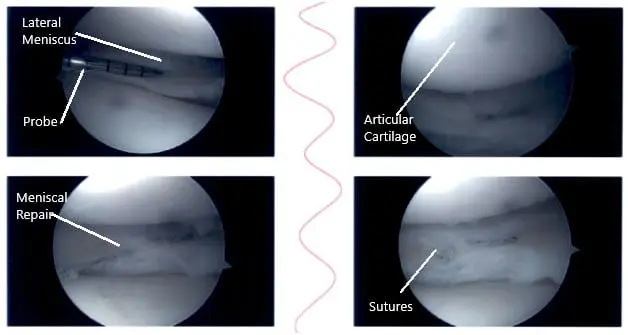

The medial entry portal was made.  The probe was inserted and the meniscus tear was again checked.  It was involving the posterior body of the medial meniscus along with the capsule.  The decision was made to repair the ramp lesion using an all-inside suture configuration.

Two curved and two reverse curved FasT-Fixes were used to complete the repair after the meniscus was abraded along with a capsule abrasion done with the shaver. The repair was found to be in a good position.

Intraoperative knee arthroscopic images 2

Intraoperative knee arthroscopic images.